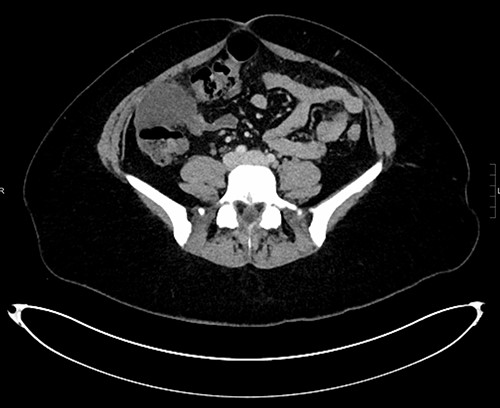

The white cell count was 10.5 × 109/l, C-reactive protein 6.8 mg/l, B-hCG negative, urine culture negative. Ultrasound (US) abdomen did not identify the appendix or the right ovary but noted a 102 × 43 × 52 mm complex multi-locular cyst. Computed tomography (CT) abdomen showed a focal low-density mass with adjacent inflammatory change anterior to the ascending colon measuring 43 × 55 × 54 mm (Figs 1–3). This mass appeared separate to the ovary and the appendix.

Coronal CT reconstruction measuring the largest dimension of mass.